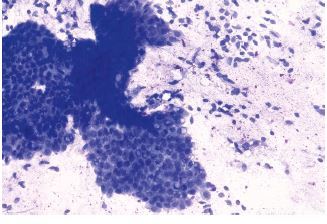

10

Q

FNA of lung lesion

A

Carcinoid